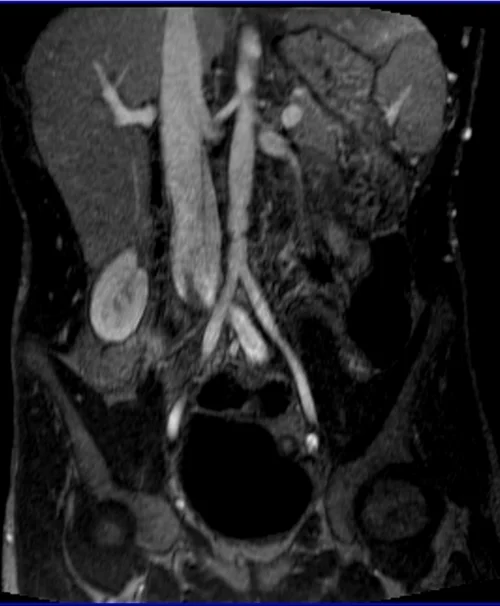

MRA Renal Arteries